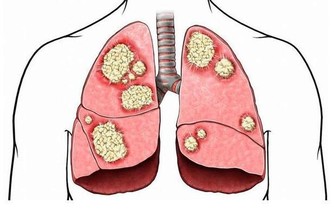

凌晨3—5點鐘醒,應該疏通肺經

連續三天以上出現凌晨3—5點鐘定時醒來,預示著肺經循行不暢。